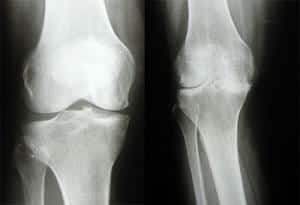

- Первая стадия деформирующего артроза проявляется легким болевым синдромом и усталостью после физической активности. Вращение и разгибание предплечья становятся затруднительными, а тонус периартикулярных мышц снижается. На рентгеновском снимке фиксируется незначительное сужение суставной щели.

- Во второй стадии артроза боль ощущается как при движении в локтевом суставе, так и в состоянии покоя. Сгибание руки в локте, особенно при отведении назад, становится сложным, что затрудняет выполнение домашних дел. При движении руки слышен хруст, сопровождающийся болевыми ощущениями. Также наблюдаются отечность и слабость мышц. На рентгене четко видны костные разрастания и деформация. Снижение качества жизни побуждает пациента обратиться к врачу.

- Третья стадия характеризуется интенсивными болями и ограничением функциональности сустава. Болевой синдром не покидает пациента даже ночью, что ухудшает качество сна. Деформация локтевого сочленения становится заметной без специальных инструментов. На рентгене видны значительные остеофиты, полное разрушение хряща и минимальное сужение суставной щели (см. фото).